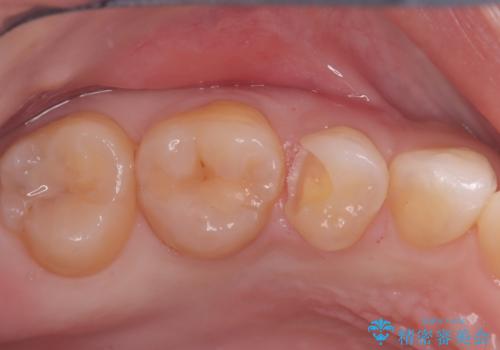

見逃しやすい小さな穴も精密に修復。自然な見た目のセラミックインレー

- 右上5番(小臼歯)の咬み合わせの面(咬合面)に小さな穴があることを主訴にご来院されました。視診およびレントゲン検査の結果、表面の穴は小さいものの、内部で虫歯が広がっていることが確認されました。患者様から「目立たないように治したい」というご希望があったため、健全な歯質を極力残しながら、審美性と耐久性に優れた**セラミックインレー(詰め物)**で修復する計画を立案しました。

治療ではまず、小さな穴から内部に広がっていた虫歯を、マイクロスコープ(歯科用顕微鏡)等を用いて精密に除去しました。虫歯を取り除いた後の空洞を整え、歯との適合性を高めるための精密な型取りを行いました。

後日、歯の色調に合わせてオーダーメイドで作製されたセラミックインレーを装着。セラミックは天然歯のような透明感があるため、修復した箇所がどこかわからないほど自然な仕上がりとなりました。